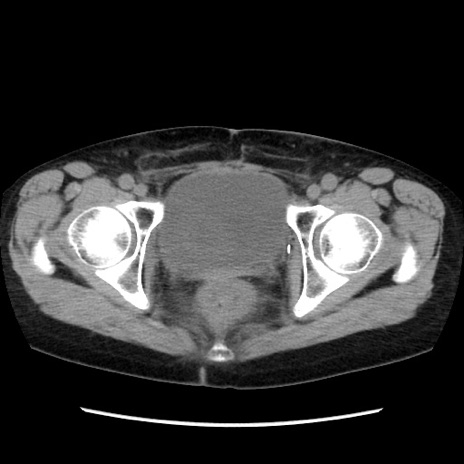

症例32(横断像)

【症例】40歳代 女性

【主訴】上腹部痛、嘔気・嘔吐

【現病歴】約9時間前頃から急に上腹部痛、嘔気、嘔吐が出現。改善しないため救急要請。

【既往歴】子宮頚癌(広汎子宮全摘術、放射線療法)、腸閉塞

【身体所見】腹部:平坦、軟、腸雑音亢進、上腹部を中心に腹部全体に圧痛あり。

【データ】WBC 8400、CRP 0.03